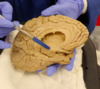

Lateral view of cerebral hemisphere (frontal pole on the right)

What structure is hidden between the temporal and parietal lobes? What fissure/sulcus is it located in?

Insula: portion of the cerebral cortex folded deep within the lateral sulcus (the fissure separating the temporal lobe from the parietal and frontal lobes) within each hemisphere of the mammalian brain.

Function of insula (N.B. part of lobe been removed in photo)

What is being pointed to? (lobes have been removed)

Insula